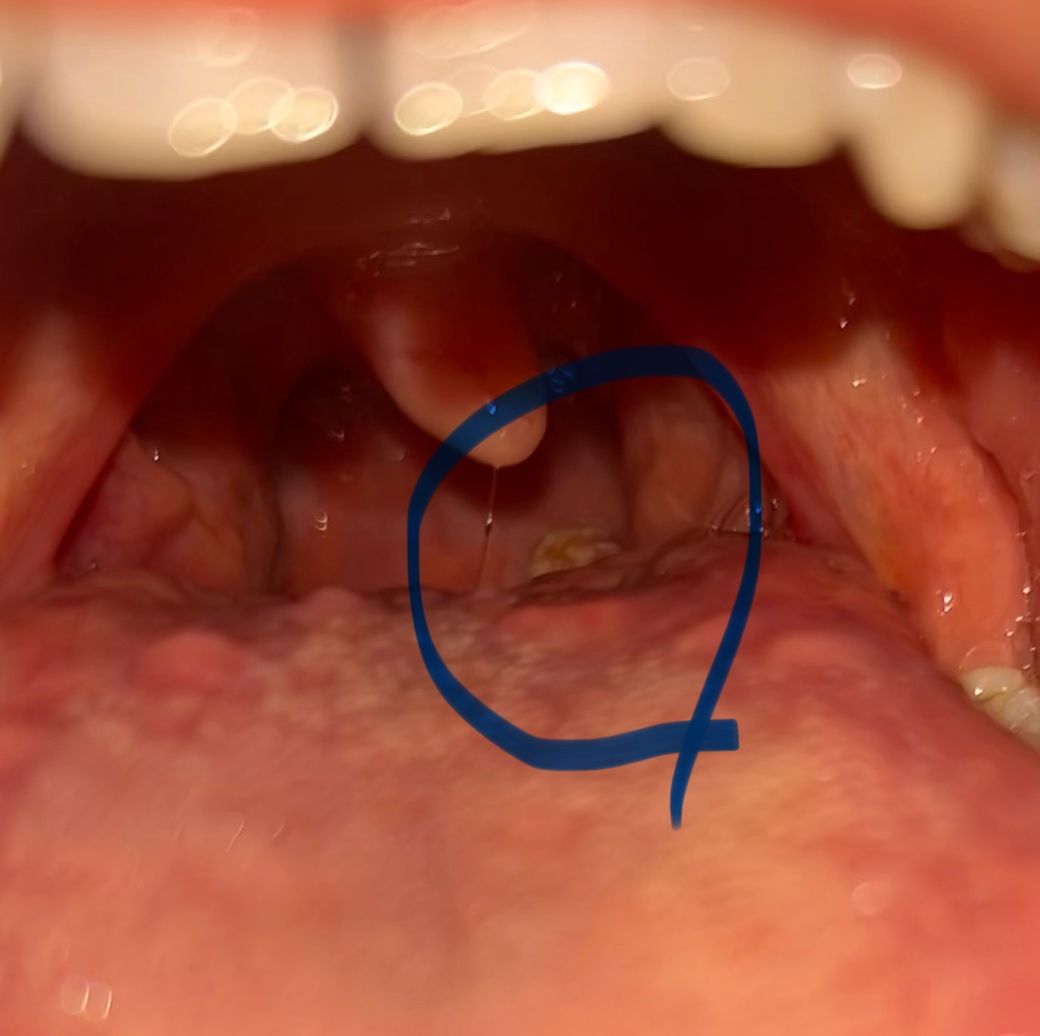

목에 있는 이건 편도선염때문인가요 뭘까요?

최근에 목이 따끔따끔하고 그래서 거울을 통해서 보니 이렇게 하얀 뭔가가 생겼더라고요

편도선염때문인지 아님 다른 문제인건지 알고 싶습니다

(평소에 편도선염이 자주 생기고 최근에는 편도결석도 생깁니다)

말씀하신 과거 병력을 고려해 보았을 때 해당 부위의 사진 상 병변은 편도선염일 가능성이 높아 보입니다. 특히 질문자님의 경우처럼 반복적으로 편도선염이 있는 겨우우에는 만성 편도선염으로 진행할 가능성이 있습니다. 이런 경우 항생제의 장기간 치료가 필요할 수 있으므로 반드시 이비인후과에 방문하셔서 현 상태에 대한 정확한 진찰 및 진단을 받으시는 것이 좋겠습니다.

목에 하얀 물질이 보인다면, 편도선염이나 편도결석과 관련이 있을 수 있습니다. 편도선염은 편도에 염증이 생겨 목 통증과 함께 부풀어 오르며, 하얀 농이 생기거나 하얀 물질이 보이기도 합니다. 편도결석은 편도에 쌓인 세균, 음식물, 세포 등이 뭉쳐 형성된 딱딱한 덩어리로, 이로 인해 불쾌한 냄새가 나기도 하며 목에 이상한 느낌이 들 수 있구요

편도결석이나 편도선염이 자주 발생한다면, 감염이나 염증이 반복될 수 있기 때문에 증상이 심해지기 전에 치료가 필요할 수 있습니다. 만약 목 통증이 계속되고 하얀 물질이 자주 보인다면, 이비인후과를 방문하여 정확한 진단과 적절한 치료를 받는 것이 좋습니다.